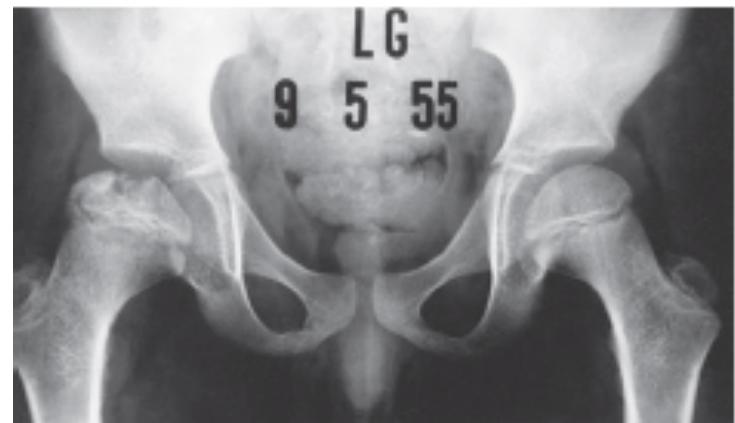

Slipped Capital Femoral Epiphysis (SCFE)

Clinical Presentation

A 13-year-old overweight boy presented to the clinic with pain in his left thigh and knee for one month. He was limping. There was no swelling and no tenderness in the thigh and knee. The hip was held in external rotation and showed limitation of internal rotation.

Q1. What is the diagnosis?

- Slipped capital femoral epiphysis (SCFE)

Q2. What is the treatment of choice?

- Fixation in situ without manipulation, and fix the other limb because there is 1/3 of cases have recurrence in the other joint

14 years old boy, limping, obese, hypogonadism

X-ray: AP and Frog lateral

Presentation: Acute: painful, Chronic: painless

Diagnosis: Slipped Capital Femoral Epiphysis (SCFE)

Signs:

- Hip externally rotates when flexed

- Limited internal rotation